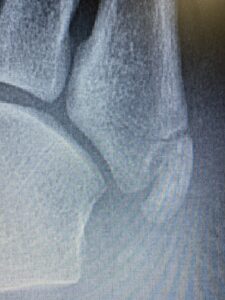

けど、第五中足骨の骨頭を触れると明らかに他の部位とは違う反応が❗️

結果、折れてました😅

CA635E37-EDE4-4CEF-8475-909A8FF544AE 85171FEB-0DD0-433A-A7F5-8381FAB181D9

この骨折、いわゆる下駄骨折って言って下駄履いて転んだらよくなるやつなんです❗️